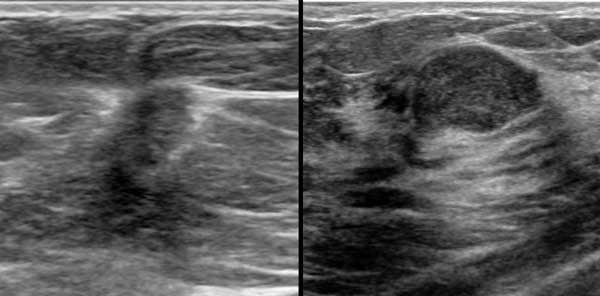

Đây là hai tổn thương hình bầu dục giảm âm.

Thoạt nhìn, chúng trông không khác nhau nhiều.

Hãy quan sát kỹ các hình ảnh và xác định những điểm khác biệt.

Tổn thương bên trái là ung thư biểu mô.

- Hình dạng bất thường

- Bờ góc cạnh và không rõ nét

- Quầng tăng âm xung quanh

- Hướng của tổn thương nghiêng về chiều dọc, không song song với da, tức là chiều cao lớn hơn chiều rộng

- Bóng cản âm phía sau

Tổn thương bên phải là u xơ tuyến vú.

- Hình bầu dục với múi nhẹ

- Bờ rõ nét

- Hướng nằm ngang, song song với da

- Tăng âm phía sau